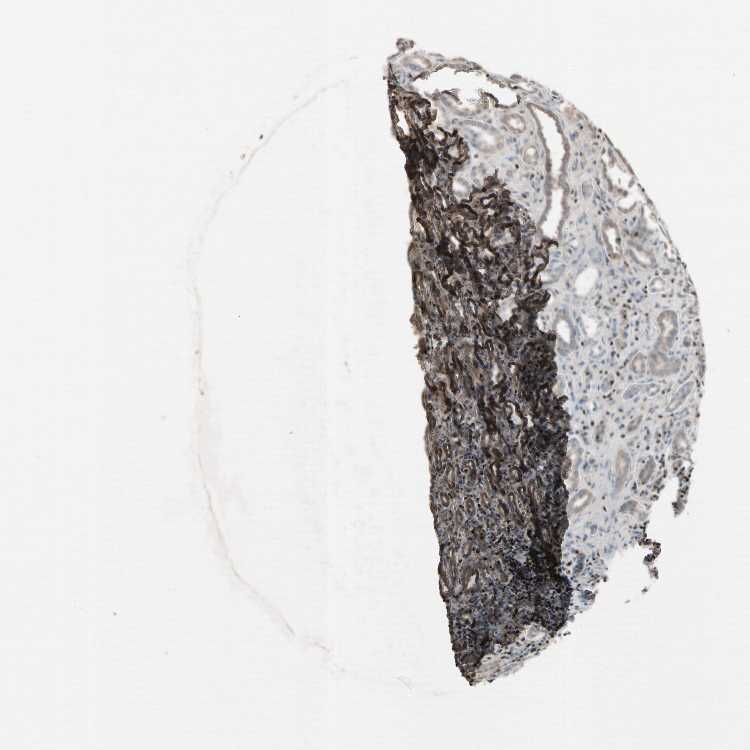

Information about each individual sample is listed below, including gender, age, a tissue section image and estimated fractions of cell types. pTPM (transcripts per million) values give a quantification of the gene abundance which is comparable between different genes and samples.

Female, age 55

Kidney sample 57 pTPM: 0.5

Cells in tubules: 70 Cells in glomeruli: 15 Fibroblasts: 10 Other cell types: 5